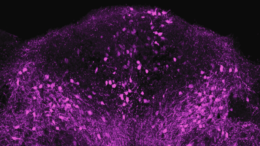

Public Health October 27, 2022 Scientists Identify the Brain Cells That Slow Us Down When We’re Sick We tend to eat, drink, and move less when we’re feeling under the weather. And we’re not alone — most animals reduce those same three behaviors when they’re fighting an…